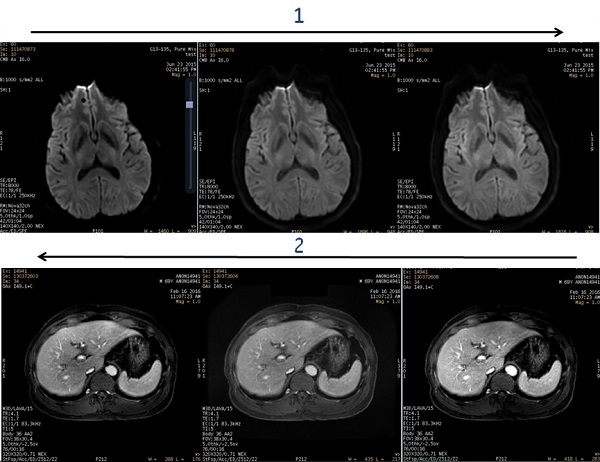

| 1 | Head example demonstrating that as the PURE Compensation value gets larger the center of image gets brighter. |

| 2 | Abdomen example demonstrating that as the PURE Compensation value gets smaller, the center of image gets darker. |